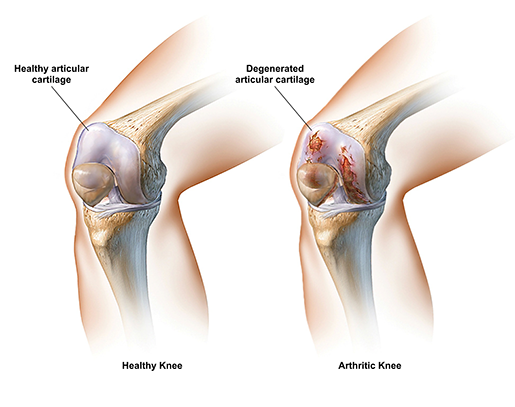

Articular cartilage repair is a specialized orthopedic procedure that restores damaged cartilage in joints such as the knee, hip, or ankle, enabling smooth, pain-free movement. Cartilage acts as a cushion between bones, facilitating effortless joint motion and absorbing impact, but once injured or degenerated, it does not heal naturally, leading to pain, stiffness, and reduced mobility. Our expert surgeons employ advanced regenerative and surgical techniques — including microfracture surgery, autologous chondrocyte implantation (ACI), and osteochondral grafting — to repair or replace damaged cartilage, preserving natural joint function and preventing progression to arthritis. Each treatment is personalized based on the extent of damage, patient age, activity level, and joint health.

Cartilage repair alleviates joint pain, restores flexibility, and improves overall mobility, allowing patients to return to active lifestyles and daily activities with comfort. Unlike joint replacement, these procedures aim to regenerate natural cartilage and preserve the patient’s own joint, making them particularly suitable for younger or highly active individuals. In addition to reducing discomfort, cartilage repair can prevent further joint deterioration, delay the need for joint replacement, and enhance long-term joint health, providing patients with lasting functional and emotional benefits.

Patients with damaged joint cartilage due to injury, overuse, or early arthritis, especially younger or active individuals, are ideal candidates for cartilage repair procedures.